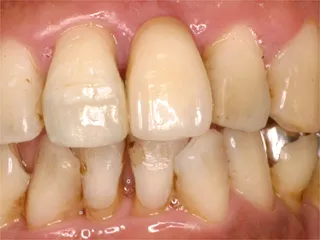

| 自費ブリッジ |

保険のブリッジ

通常のブリッジでは 正面から金属が見えてしまいますが ピンレッジでは見えません ■長所 ・金属が見えない ■短所 ・前後の歯を裏だけ削る ・前後の歯が健全な場合のみ可能 ・高い |